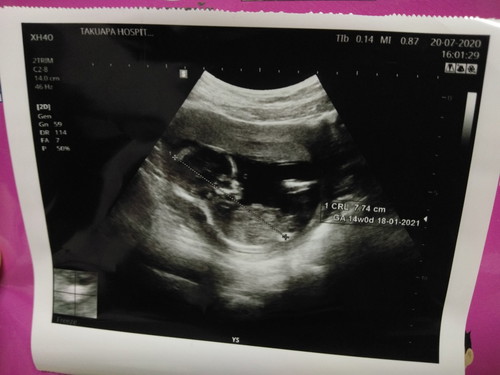

ตั้งครรภ์ 14 สัปดาห์

คุณแม่ที่ตั้งครรภ์ 14 สัปปดาห์ผลอัลตร้าซาวด์แตกต่างกันไหมค่ะ